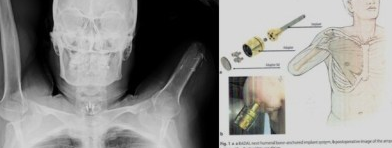

The surgery took place on November 28 and was performed by orthopedic surgeon Dr. Stelios Hadjichristofis. During the operation, doctors placed a BADAL cylindrical implant into the upper arm. Once that fully stabilizes over the next few weeks, the patient will begin slowly adding weight and learning how to use the new arm before final adjustments are made.

This isn’t just any prosthetic. The bionic limb includes a myoelectric elbow, wrist, and a multi-jointed hand, all controlled by the body’s own muscle signals. In simple terms, it should allow the patient to perform a wide range of movements that traditional prosthetics simply can’t match.